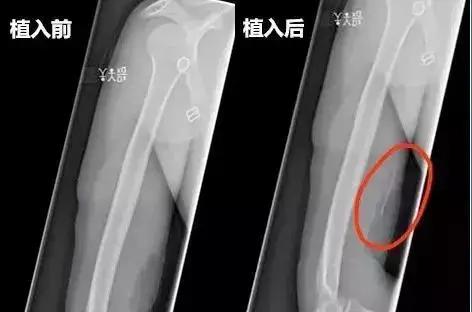

▲x射线下植入前后对比图